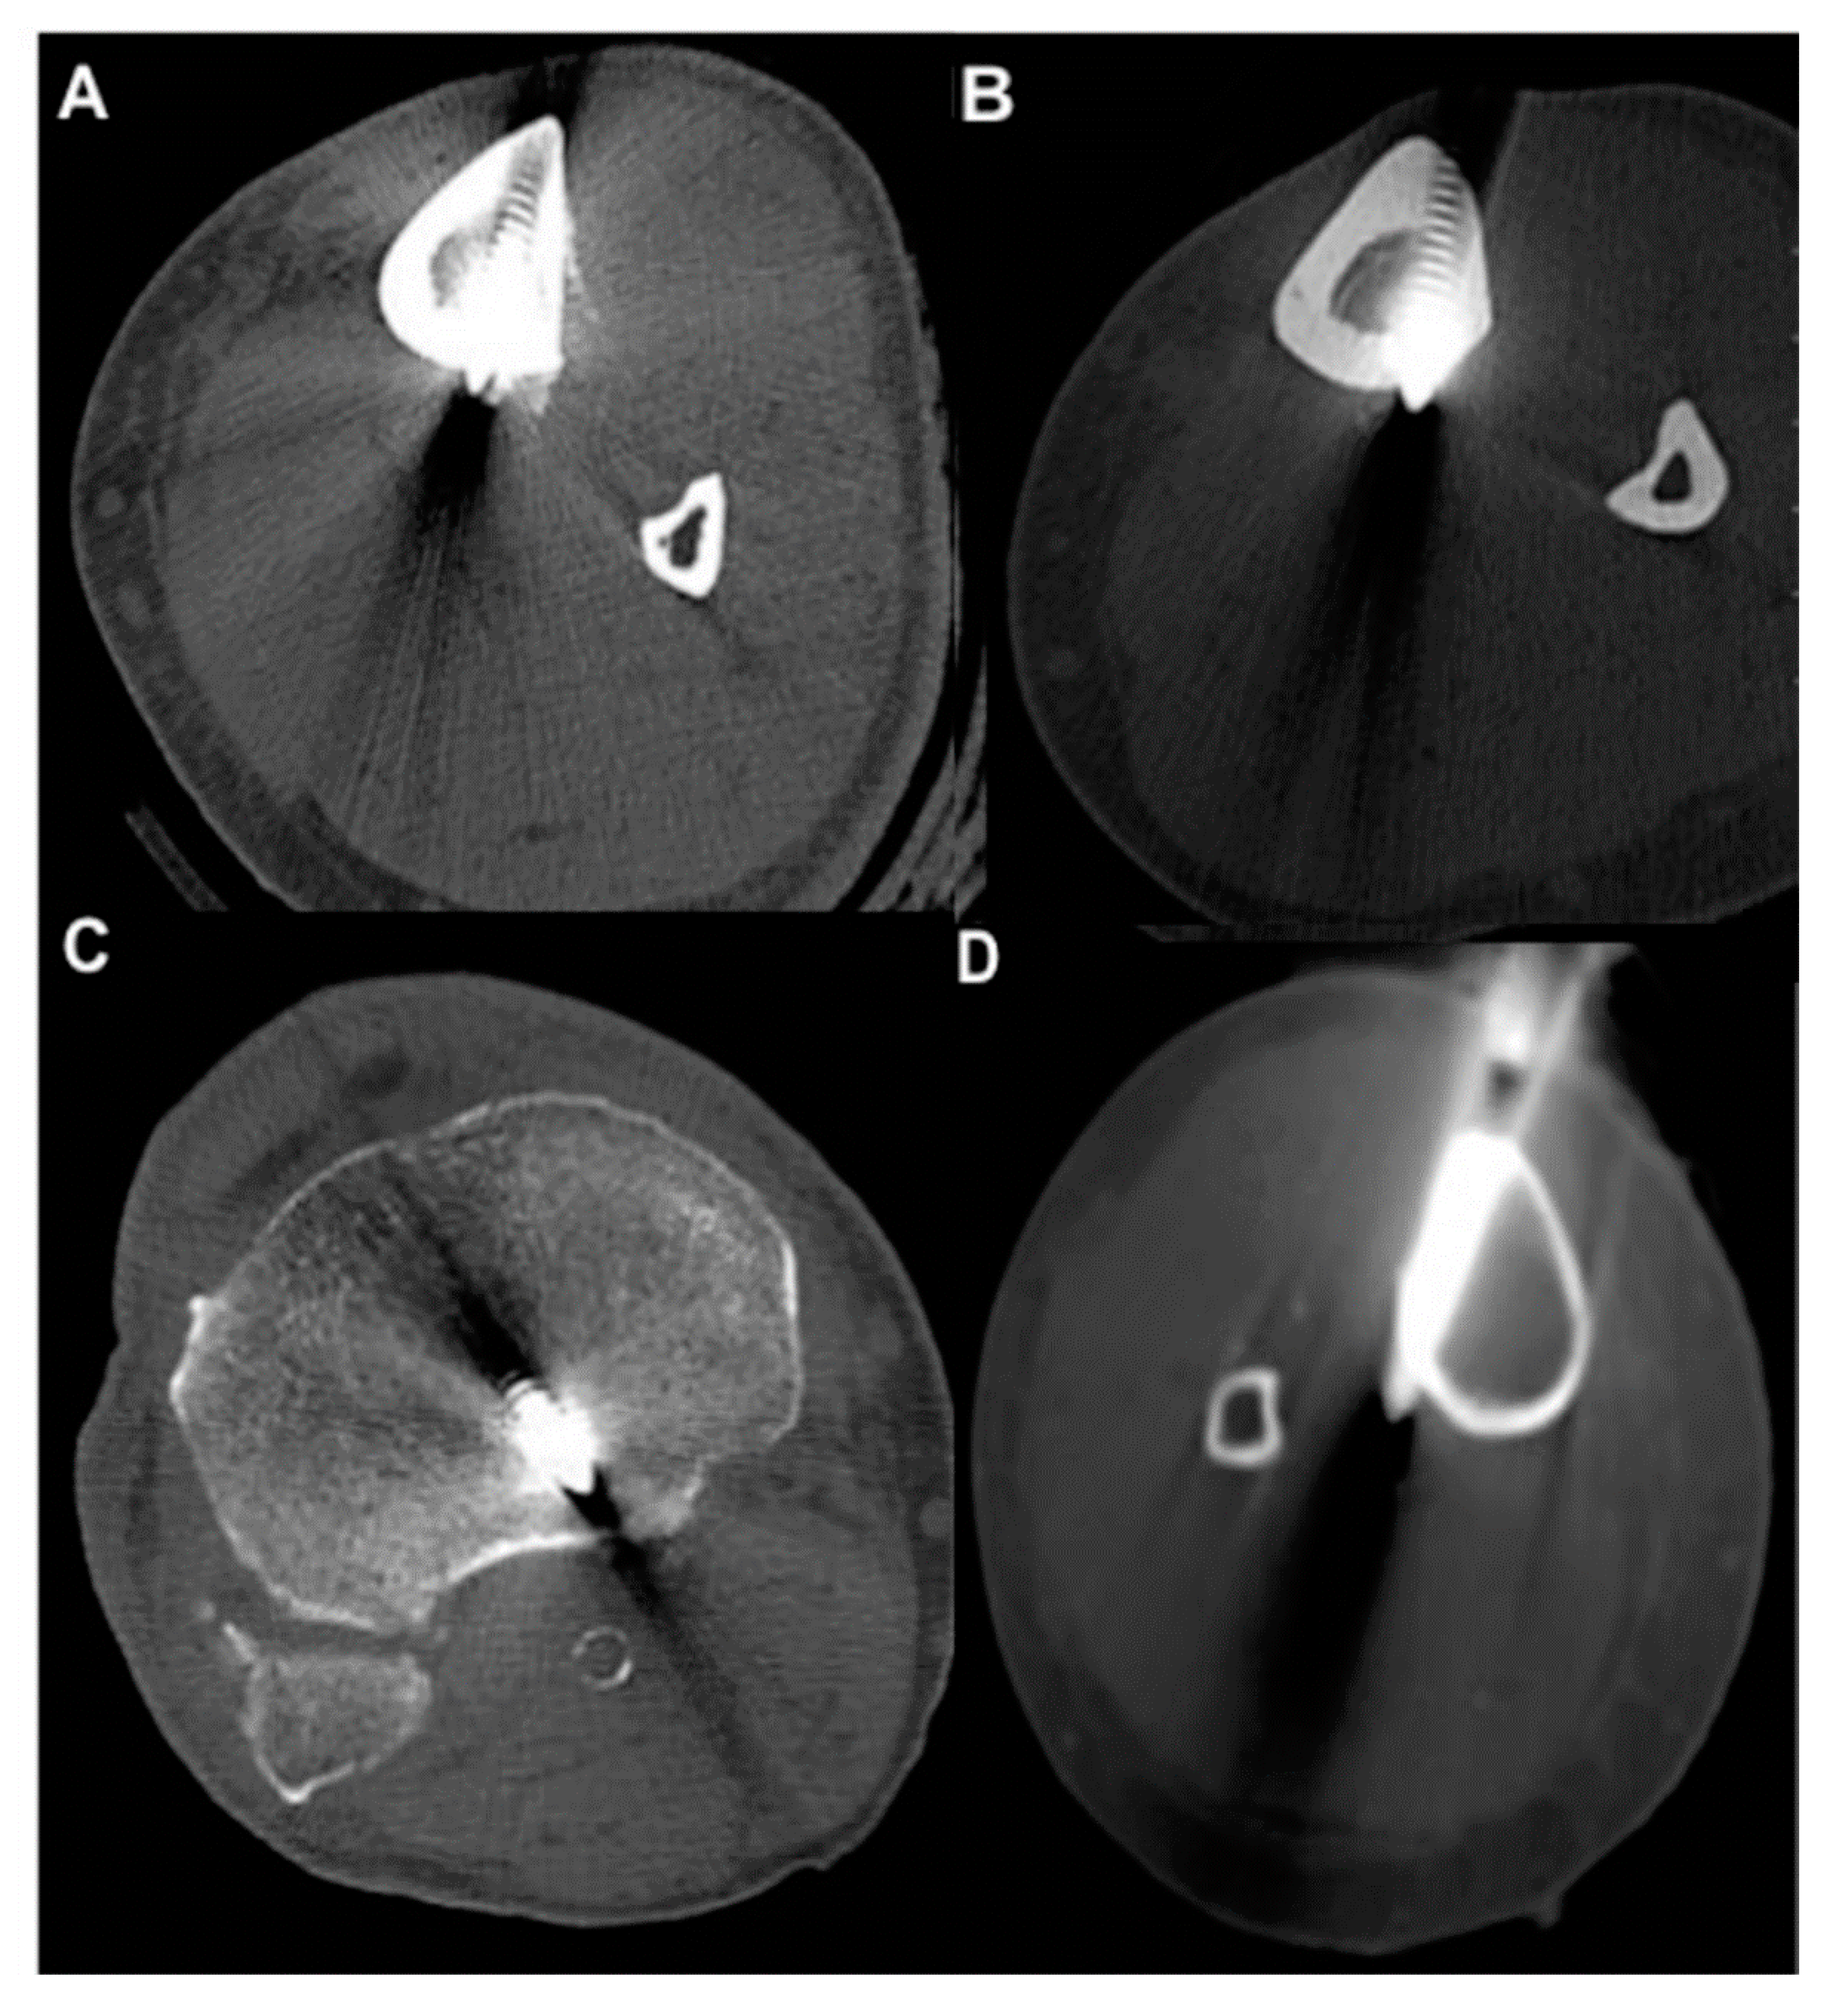

- Pin characteristics (orientation of pin application: anteromedial/tibial crest, anterolateral) and cortical position of the pins (bicortical/monocortical/transcortical) (Figure 2).